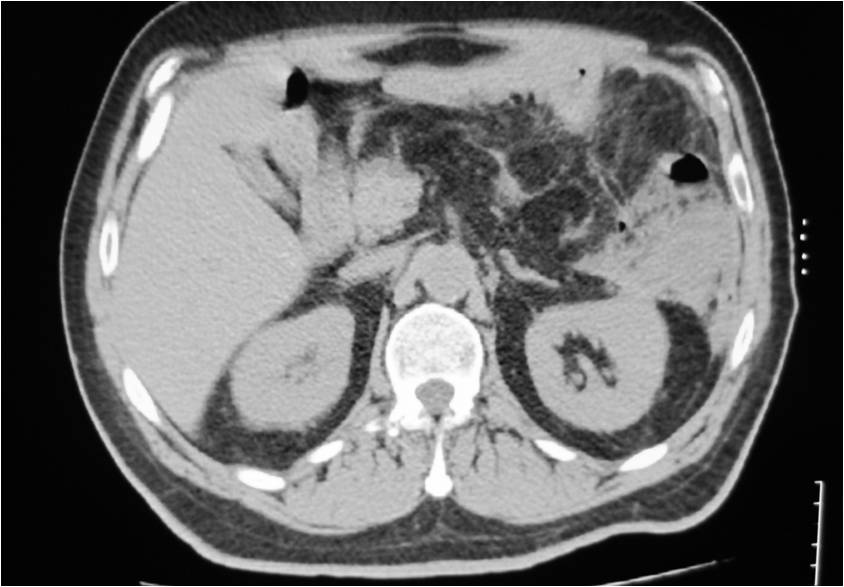

- Abscess post left hemicolectomy

- Successful placement and drainage